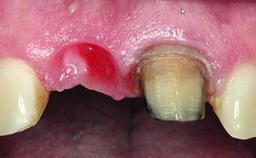

A healthy 37-year-old female patient was referred for a consultation on the replacement of missing tooth 21 with an implant-supported restoration. She stated that several years previously the tooth had been traumatically avulsed following a motor vehicle accident. The tooth was replaced with a three-unit fixed partial denture (FPD) immediately afterwards. Over time, she became disillusioned with the FPD and looked for a different option, including orthodontic therapy. She presented still in her orthodontic appliances, with the pontic sectioned free from the FPD but attached to the archwire. Her orthodontist felt that orthodontic treatment had been successfully completed, but nevertheless referred her before removing the appliances in case adjustments were necessary.

Bone Volume Deficient horizontally, allowing simultaneous augumentation

Esthetic Risk High